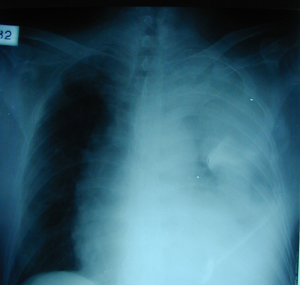

Εικόνα 2

Οπισθιοπροσθία ακτινογραφία του θώρακος μετά από προσπάθεια εκκένωσης του υγρού με την εισαγωγή σωλήνα παροχέτευσης θώρακος, αφού είχε τεθεί η διάγνωση αιμοθώρακος με διαγνωστική παρακέντηση. Ο έλεγχος του αίματος έδειξε ότι υπήρχε μεγάλη παράταση του χρόνου προθρομβίνης από τα αντιπηκτικά.